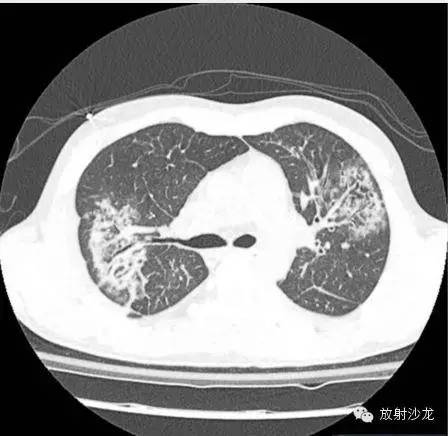

第一次CT:

(第一次胸片示两肺中野及右肺下野多发斑片状高密度影。胸部CT示多发斑片状磨玻璃样密度增高影以及实变影,同时伴有小叶间隔的增厚。其中有些病灶部分表现为“铺路石征”。两周后CT随访显示这些病灶的密度和范围都增大。电视辅助胸腔镜肺活检下,活检标本病理诊断结果为急性纤维素性机化性肺炎。上述病变经高剂量糖皮质激素治疗三周后明显改善。)

PS:铺路石征(Crazy-paving appearance):系磨玻璃影的背景下同时伴有网格状或细网格状小叶间隔和小叶内间隔增厚。